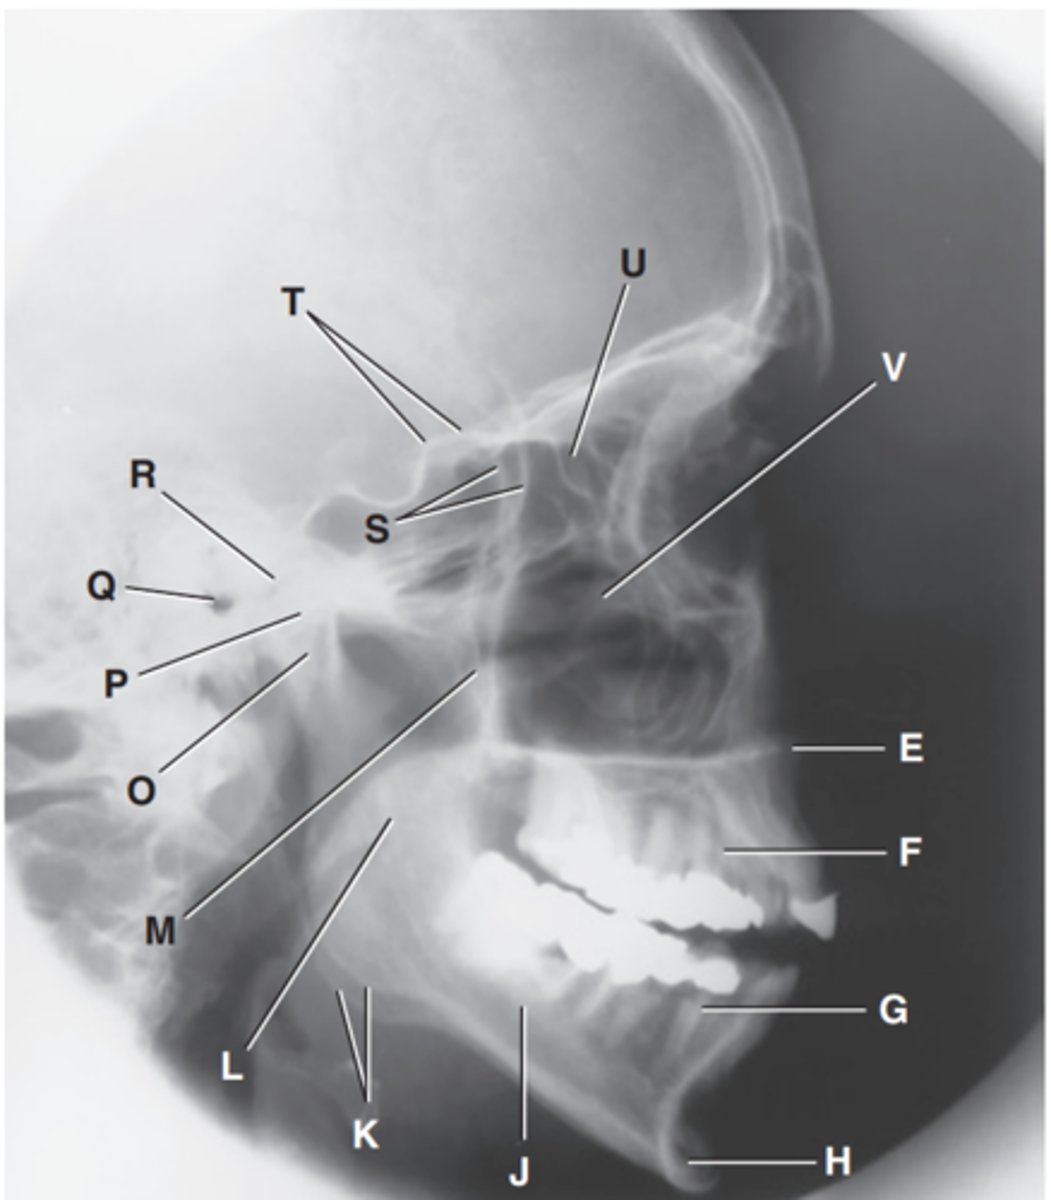

Zygomatic arch

Label A

Right zygomatic bone

Label B

Right nasal bone

Label C

Frontal process of right maxilla

Label D

Anterior nasal spine

Label E

Alveolar process of maxilla

Label F

Alveolar process of mandible

Label G

Mentum or mental protuberance

Label H

Mental foramen

Label I

Body of mandible

Label J

Angle (gonion)

Label K

Ramus of mandible

Label L

Coronoid process

Label M

Mandibular notch

Label N

Neck of mandibular condyle

Label o

Condyle or head of mandible

Label P

EAM

Label Q

TM fossa of temporal bone

Label R

Greater wings of sphenoid

Label S

Lesser wings of sphenoid with anterior clinoid processes

Label T

Ethmoid sinuses between orbits

Label U

Body of maxilla containing maxillary sunuses

Label V